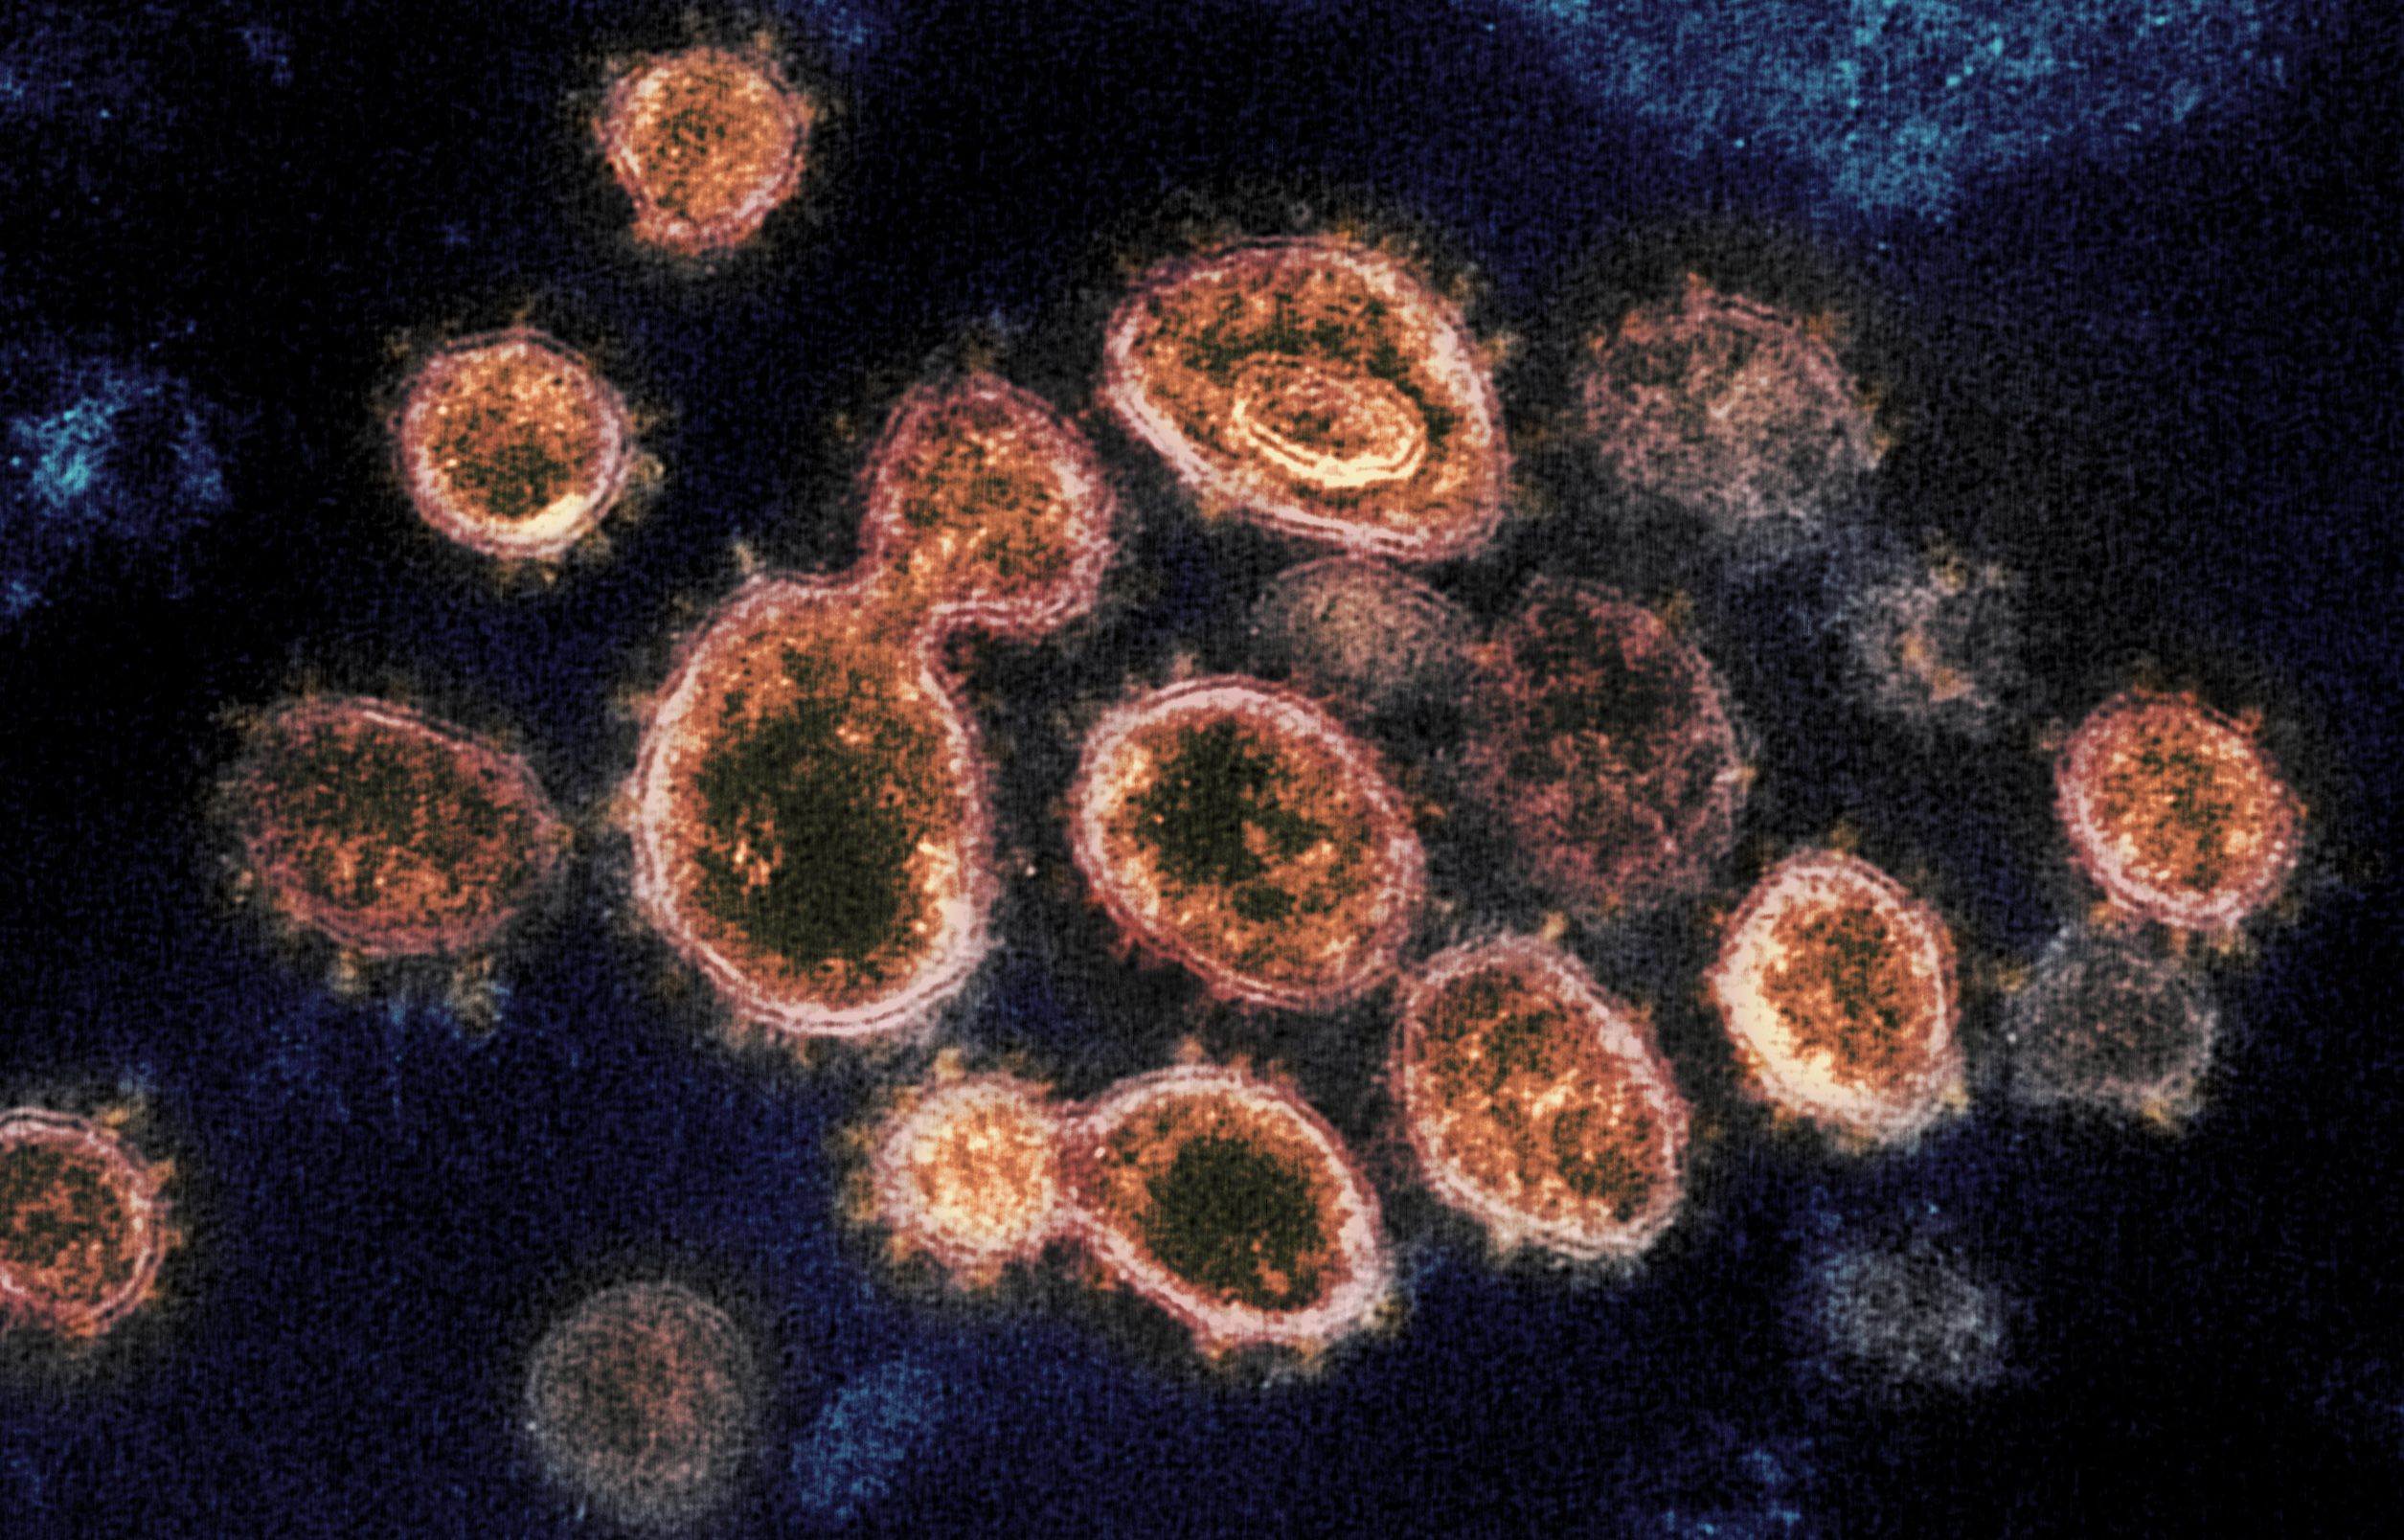

Фотографии объектов и элементов, связанных с цифрой 3

Раздел: Картинки на заметку